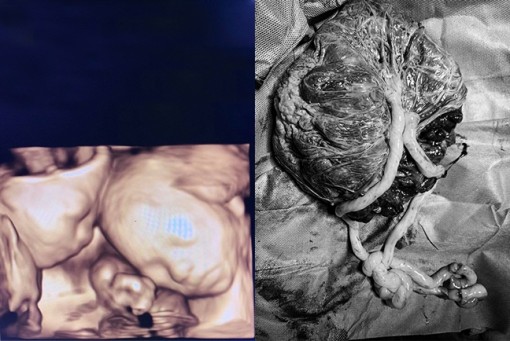

• Mổ cứu 2 bé trai song thai 'tam tai' 'độc nhất vô nhị' trong sản khoa Việt Nam

Sản phụ T. mang thai 2 bé song sinh chung một buồng ối, một bánh nhau, dây rốn xoắn quấn nhiều vòng, bị nhau tiền đạo, cài răng lược. Từ lúc bào thai thành hình, 3 mẹ con chị T. luôn đối diện nguy cơ tử vong.